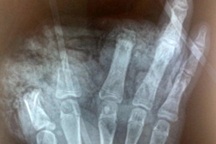

Quạt tích điện phát nổ (Ảnh: Cắt từ clip).